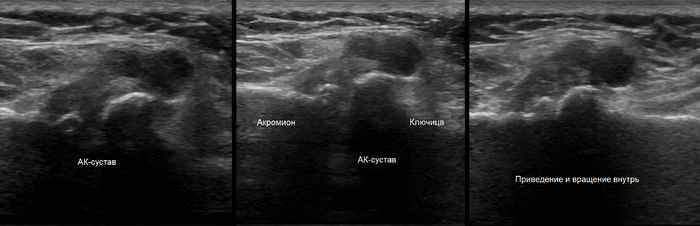

УЗИ - может подтвердить артроз, но лучше оценивает мягкие ткани (сухожилия, связки, мышцы, хрящи), можно увидеть наличие воспаления в суставе, патологию сухожильно-связочного аппарата.

Поражение АКС на УЗИ.